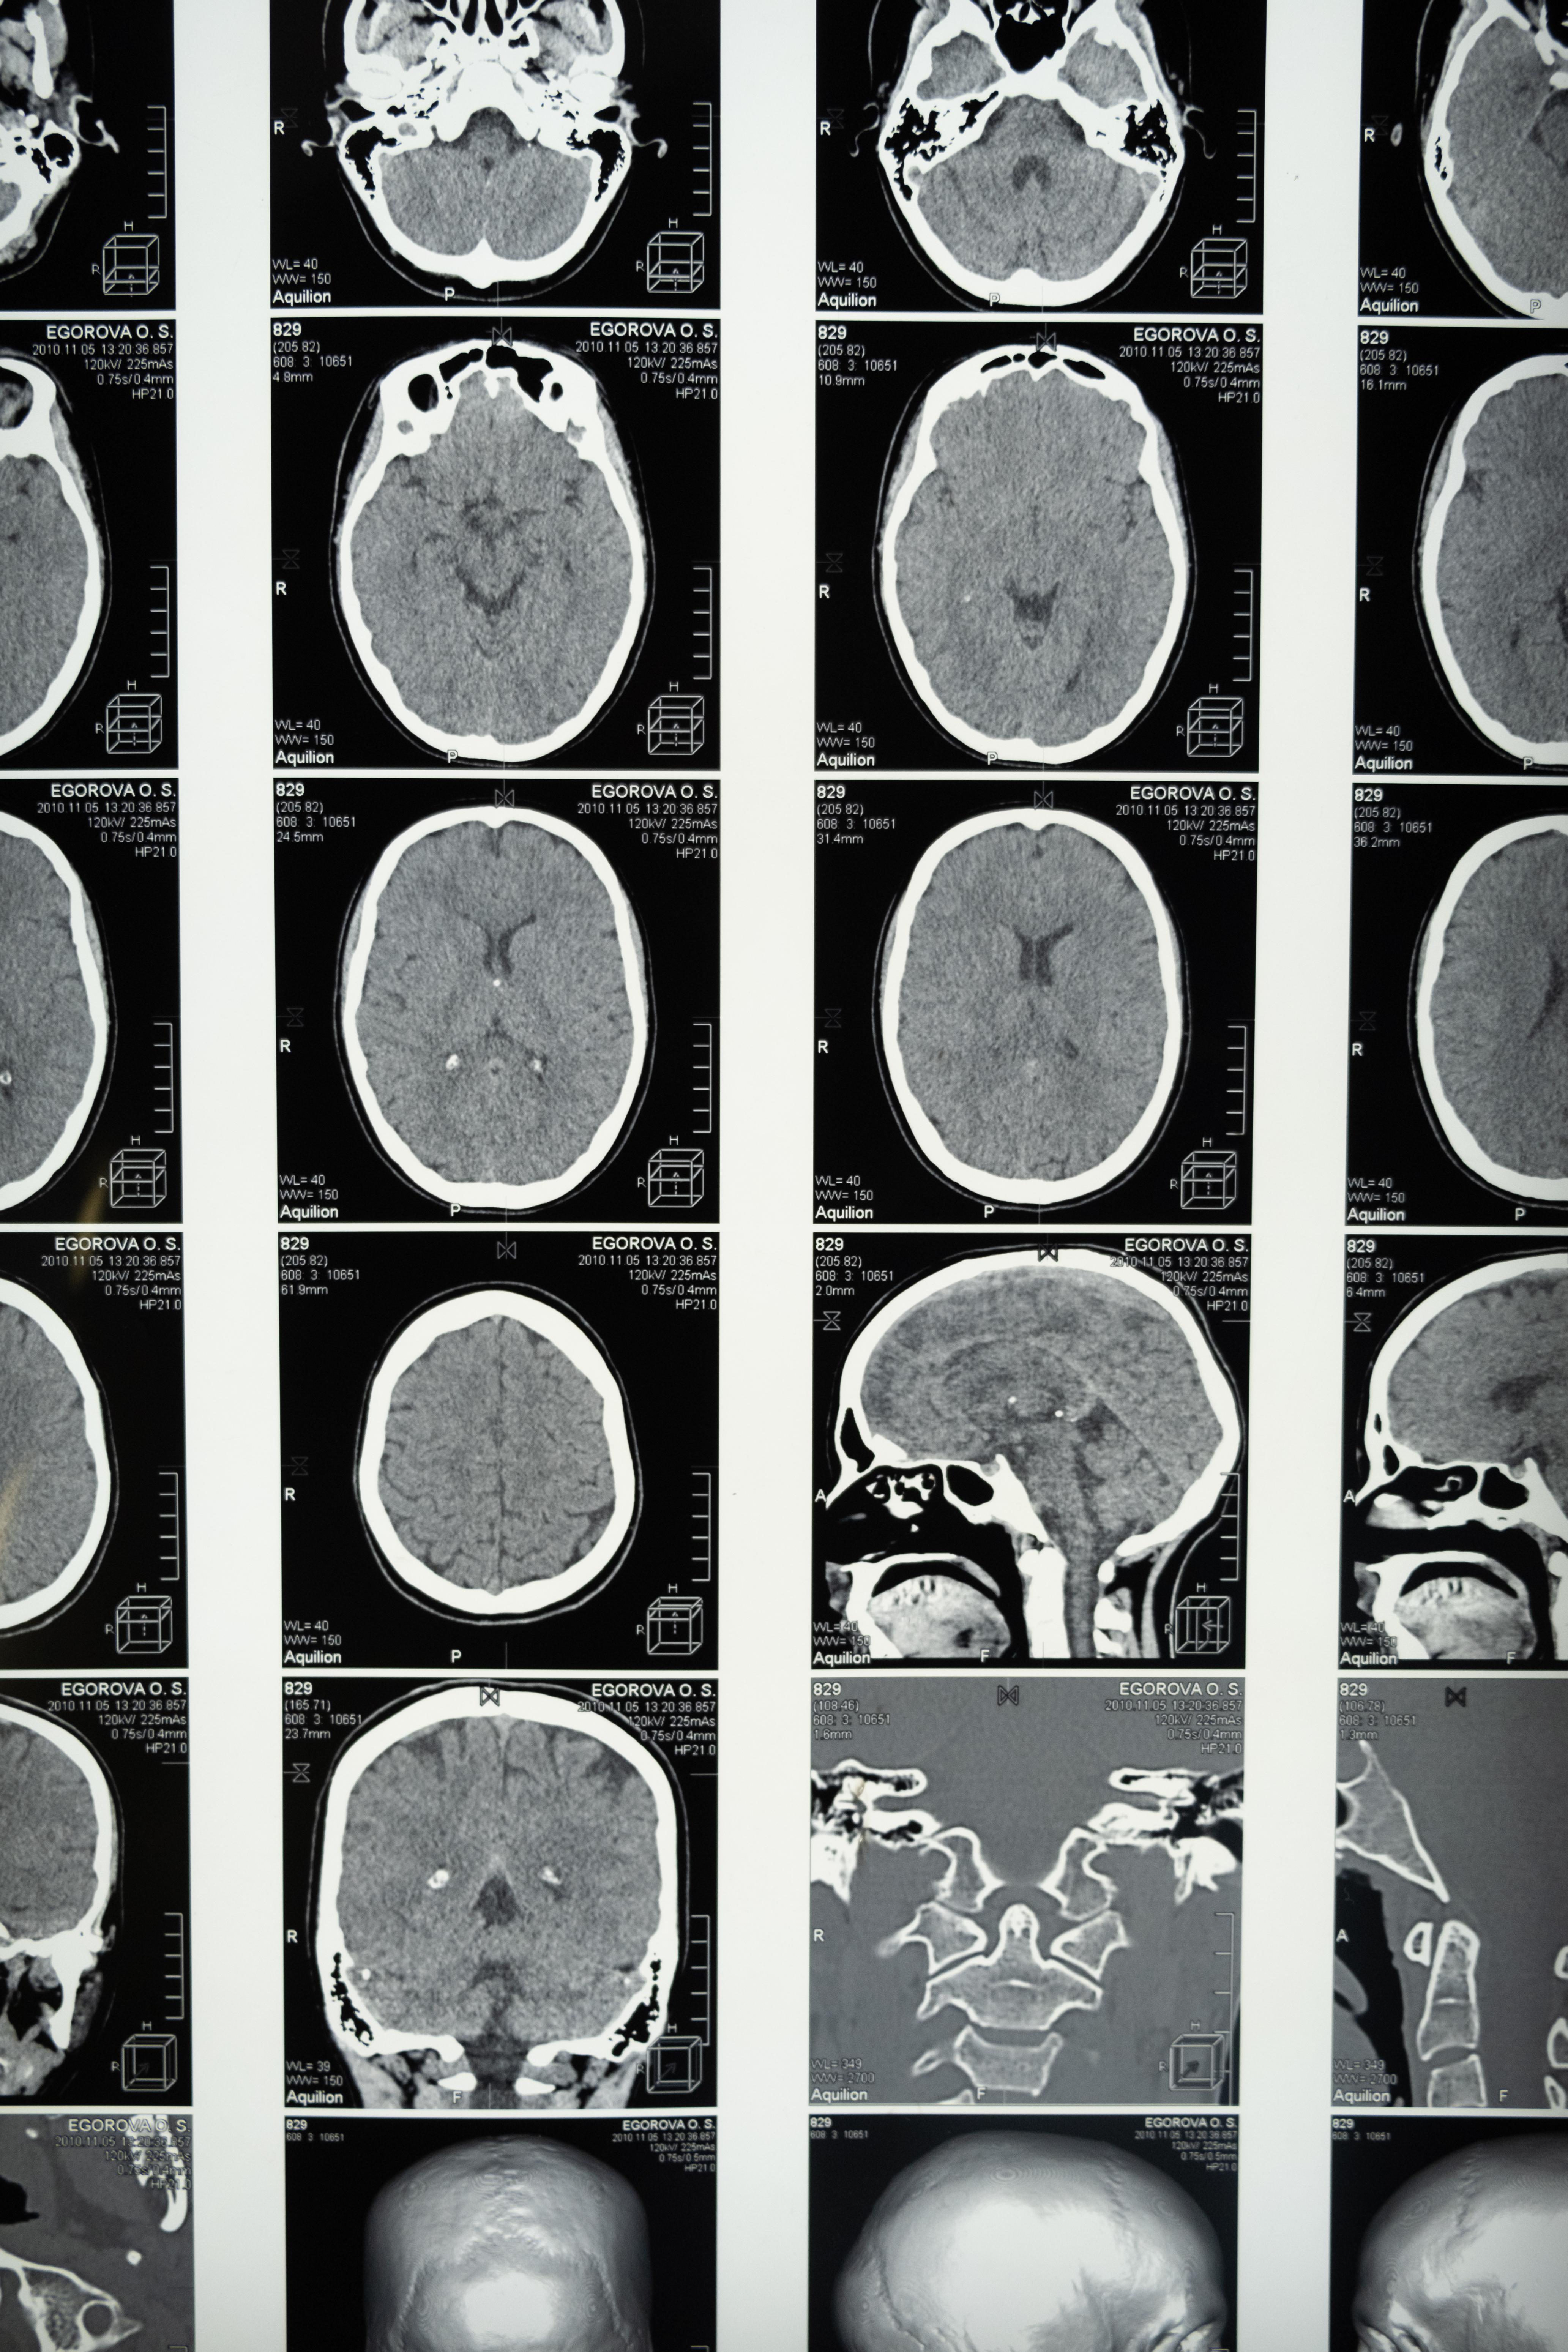

wallpaperaccess.comWhat A CT Scan Shows Of The Head & Brain

wallpaperaccess.comWhat A CT Scan Shows Of The Head & Brain